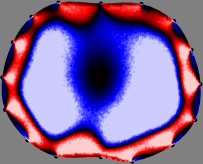

Figs. 3 and 4 compare the performance of the proposed FER method in (20) with the standard regularized least-squares method ((19) when is the identity matrix). The regularization parameter of the standard method was heuristically chosen for its best performance, and the parameter of the FER method was set to be one of three different values . The injection current was 1 mA at 100 kHz, and the frame rate was 9 frames per second. The reference frame at was obtained from the maximum expiration state. The measured data, , represent the voltage differences between each time and . The blue regions, which denote where conductivity decreased by inhaled air, increased during inspiration and decreased during expiration. The FER method with was clearly more robust than the standard method that produced more artifacts originated from the inversion process.

| Standard | |

||||||||||

| FER () | |

| FER () | |||||||||||